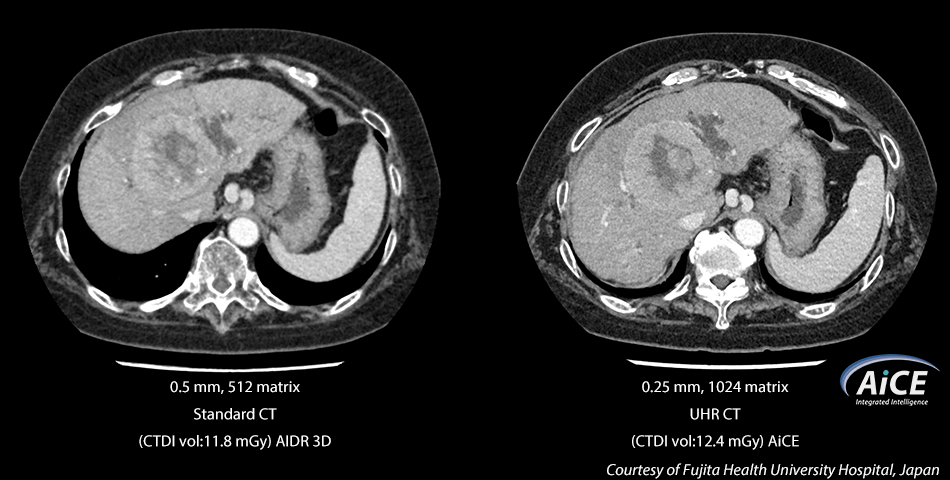

The Aquilion Precision introduces a revolutionary approach to CT reconstruction that leverages Deep Learning Neural Networks specifically trained to perform one task – reconstruct images that are sharp, clear, and distinct.

Known as AiCE, this deep learning reconstruction network is trained on an advanced Model-Based Iterative Reconstruction (MBIR) algorithm to produce low noise, natural texture, and 0.25 mm, 1024 matrix Ultra-High Resolution CT images several times faster than clinical MBIR today.